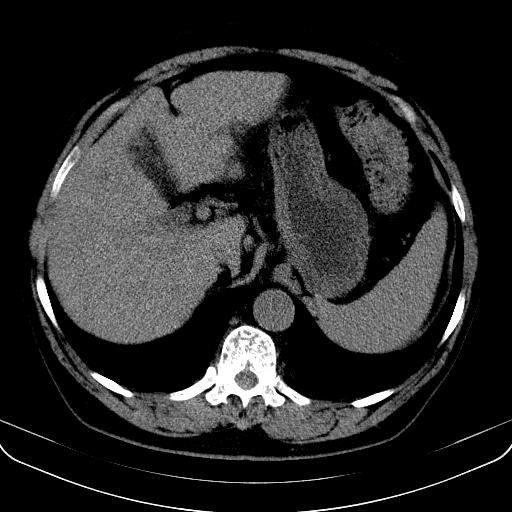

以下是引用jia119在2008-3-5 13:31:00的发言:[br]肝内多发片状低密度影,密度不均,我还是考虑肝ca可能,另肝内小囊肿,胆囊增大。

以下是引用形影不离在2008-3-5 12:18:00的发言:[br]肝硬化伴门脉高压征,肝内占位待排,增强再说.

以下是引用随光逐影在2008-3-5 21:11:00的发言:[br]肝硬化伴门脉高压(食管下段静脉曲张),肝癌不排除。建议:行ct增强扫描检查。

以下是引用同在2008-3-5 13:56:00的发言:[br]考虑肝癌可能性大,胆囊增大.